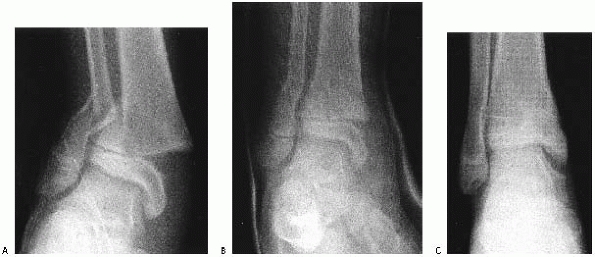

swelling only about the ankle, anteroposterior, mortise, and lateral

radiographs centered over the ankle may provide sufficient information

to plan treatment. Although obtaining views of the joint above and

below is recommended for most fractures, obtaining a film centered over

the midtibia to include the knee and ankle joints on the radiographs

significantly decreases the quality of ankle views and is not

recommended.

mortise view of the ankle is essential in addition to anteroposterior

and lateral views. On a standard anteroposterior view, the

lateral

portion of the distal tibial physis is usually partially obscured by

the distal fibula. The vertical component of a triplane or Tillaux

fracture can be hidden behind the overlying fibular cortical shadow.107 A study by Vangsness and coworkers186

found that diagnostic accuracy was essentially equal when using

anteroposterior, lateral, and mortise views compared with using only

mortise and lateral views. Therefore, if only two views are to be

obtained, the anteroposterior view may be omitted and lateral and

mortise views obtained.

described two special views designed to detect avulsion fractures from

the lateral malleolus that are not visible on routine views and to

distinguish whether they represent avulsions of the anterior

tibiofibular ligament or the calcaneofibular ligament attachments. The

anterior tibiofibular ligament view is made by positioning the foot in

45 degrees of plantarflexion and elevating the medial border of the

foot 15 degrees. The calcaneofibular ligament view is obtained by

rotating the leg 45 degrees inward.